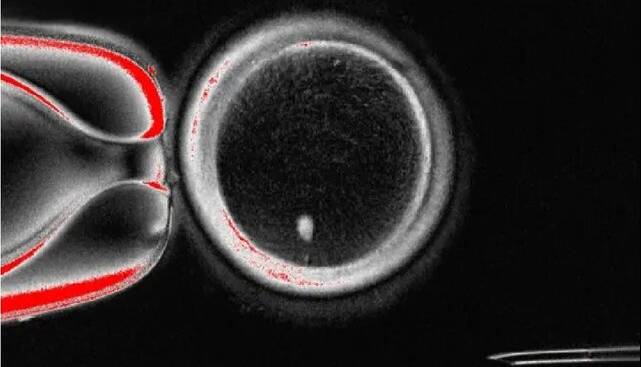

آنها هسته یک سلول پوست را به یک تخمک اهدایی که هسته آن جدا شده بود، پیوند زدند. سیتوپلاسم تخمک اهدایی باعث شد هسته سلول پوست نیمی از کروموزومهای خود را دور بریزد و «میوز» را تقلید کند.

نتیجه، یک تخمک هاپلوئید بود که میتوانست از طریق لقاح مصنوعی(IVF) استاندارد با اسپرم لقاح داده شود و جنینهایی با ورودی ژنتیکی برابر از هر دو والدین تشکیل دهد.

محققان در این مطالعه، ۸۲ تخمک عملکردی تولید کردند و آنها را با اسپرم لقاح دادند. در حالی که اکثر آنها در مرحله ۴ تا ۸ سلولی به دلیل ناهنجاریهای کروموزومی متوقف شدند، حدود ۹ درصد روز پس از لقاح به مرحله بلاستوسیست رسیدند.